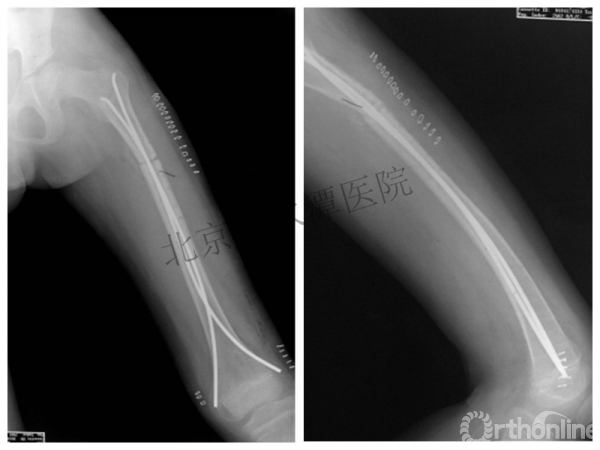

男孩、9岁,滑雪受伤,胫腓骨螺旋形骨折(粉碎性)

这个病例郭教授在积水潭医院骨科高研班时多次讲到,也在互动交流中惊人地看到,了解到现实之令人难以想象!

手法整复,石膏制动!

整复后7天

儿童具备强大的愈合潜力,同样也有极强的塑形能力

某种情况下,The best treatment is no treatment! 最佳治疗反而是不治疗!因为很多骨折依靠儿童强大的塑形能力和特点完全可以得到满意的结果!